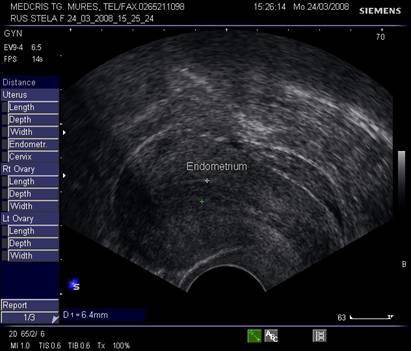

Endometrul situat in centrul uterului are contrast bine delimitat fata de corpul uterin, ecogenitatea endometrului este mai mare decat a miometrului. Vasele de la nivelul miometrului - endometrului dau o zona de contrast relativ anecogena fata de miometru - endometru.

Endometrul - grosimea sa este apreciata in sectiune longitudinala. Masurarea se va face de la interfata miometru - endometru la interfata identica, opusa, de pe peretele celalat uterin. Maxim acceptat normal este de 1,5 cm in perioada de premenopauza.[5] Postmenopauza in mod normal nu depaseste 5 mm, de obicei este atrofic si apare ca o imagine ecogena lineara. Daca apare o colectie anecogena postmenopauzala intrauterina, prin atrofie cervicala, aceasta colectie nu trebuie sa fie masurata la calculul grosimii endometriale.[2,6]

Grosimea endometrului este de circa 1-2 mm la inceput de faza proliferativa, de cca 5 mm in ziua 10 -11, cu 1 zi preovulator cca 10 - 12 mm,apoi stagneaza, toate acestea la un ciclu menstrual de 28 zile.[2,6]

Fig. nr.361. Endometru in faza de secretie incipienta